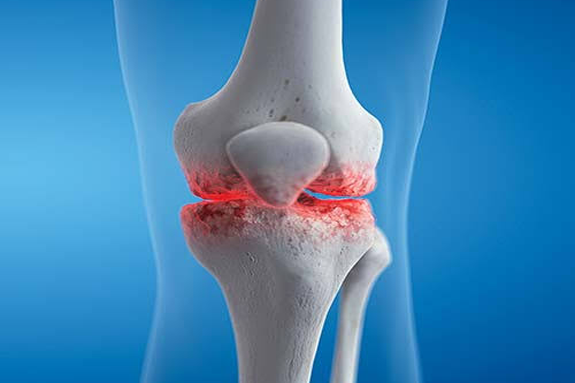

Knee Replacement

I went there for my knee trauma. Dr. Nikhil explained me very well. I took his treatment for 3 months. Now I am fine like before.. Thank you so much..!